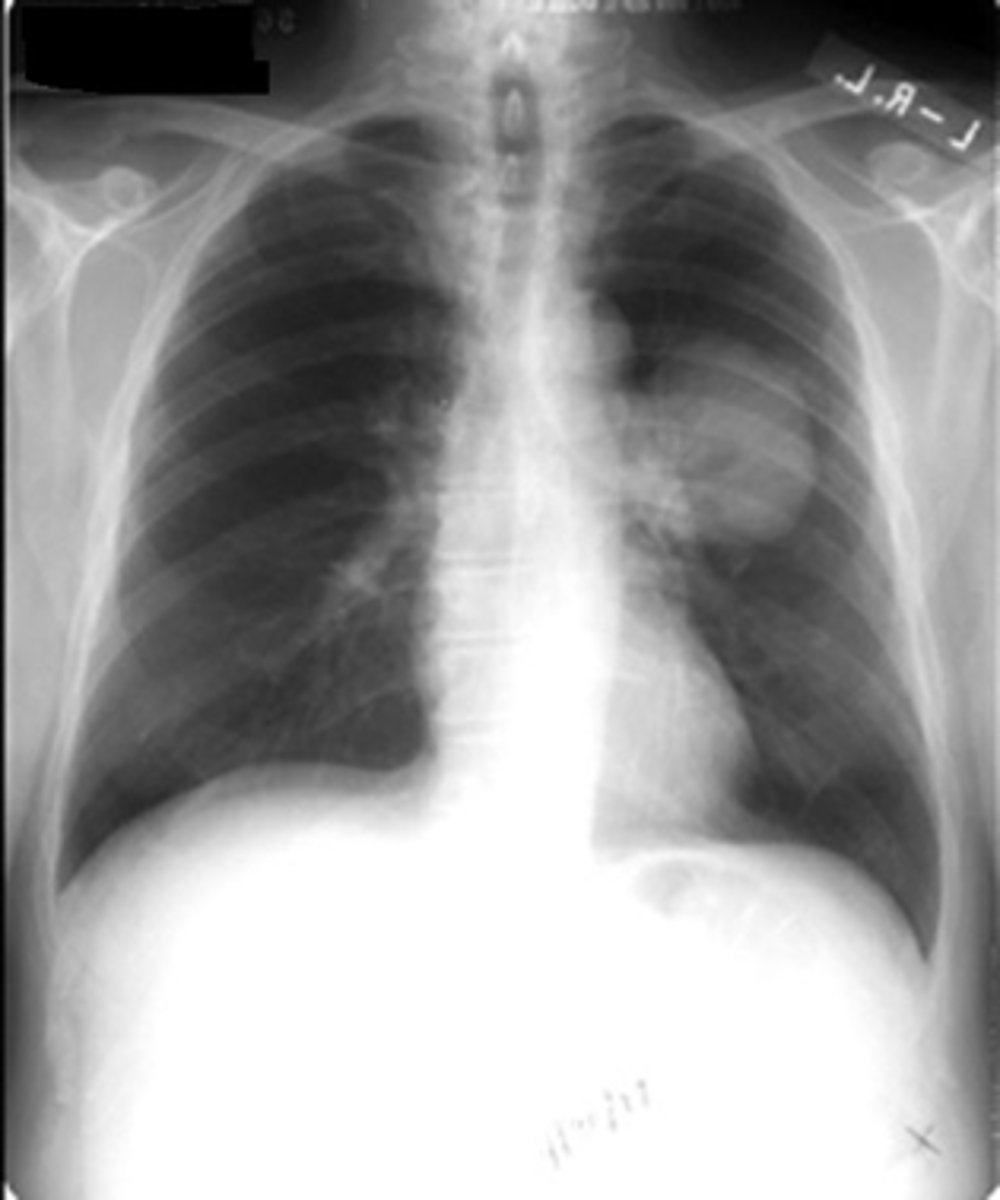

air bronchogram- alveolar consolidation LUL